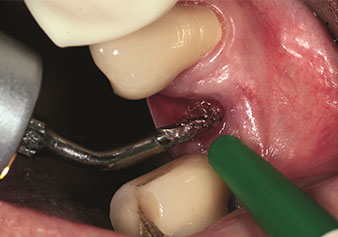

Gestion alvéolaire

Une application souvent sous-estimée est l’extraction atraumatique de racines dentaires ou de fragments radiculaires dans le cadre d’une gestion alvéolaire. Les périotomes à denture fine, qui sont actuellement disponibles en deux versions (EX1 et EX2 de W&H), peuvent également être utilisés pour extraire facilement des dents qui ont subi un traitement endodontique spécifique préalable ou des racines ankylosées. On obtient des alvéoles d’extraction dans lesquelles à la fois les tissus durs et les tissus mous sont entièrement préservés.

Ceci instaure des conditions optimales pour un traitement implantaire ultérieur ou immédiat (Figures 1 et 2 fournies avec l'autorisation du Dr Torsten Conrad, Bingen

am Rhein).